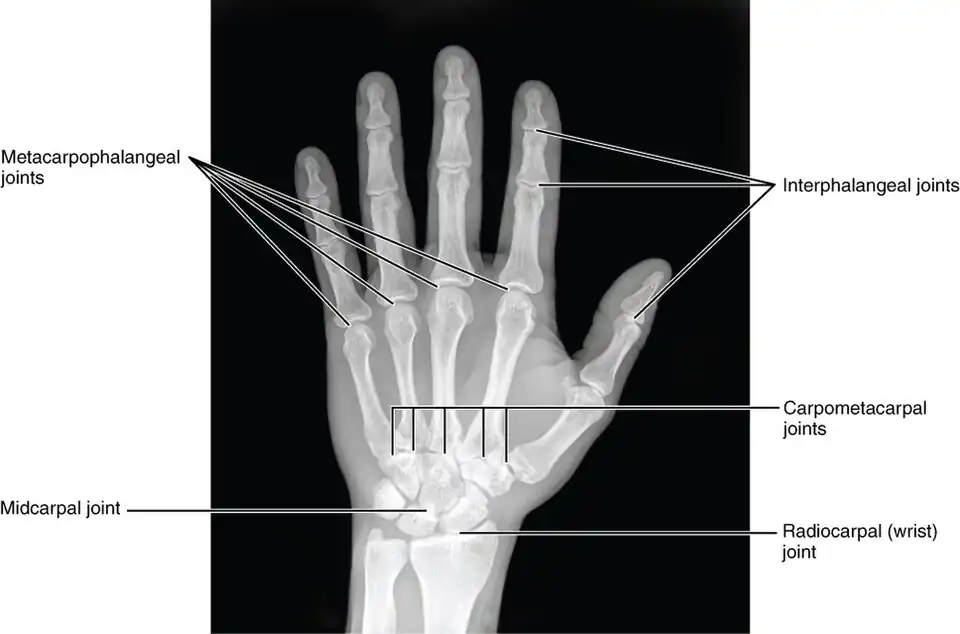

In human anatomy, the metacarpal bones or metacarpus, also known as the "palm bones", are the appendicular bones that form the intermediate part of the hand between the phalanges (fingers) and the carpal bones (wrist bones), which articulate with the forearm. The metacarpal bones are homologous to the metatarsal bones in the foot.

Each metacarpal bone consists of a body or shaft, and two extremities; the head at the distal or digital end (near the fingers), and the base at the proximal or carpal end (close to the wrist).

Articulations

Besides the metacarpophalangeal joints, the metacarpal bones articulate by carpometacarpal joints as follows:

1. the first with the trapezium;

2. the second with the trapezium, trapezoid, capitate and third metacarpal;

3. the third with the capitate and second and fourth metacarpals;

4. the fourth with the capitate, hamate, and third and fifth metacarpals;

5. and the fifth with the hamate and fourth metacarpal;